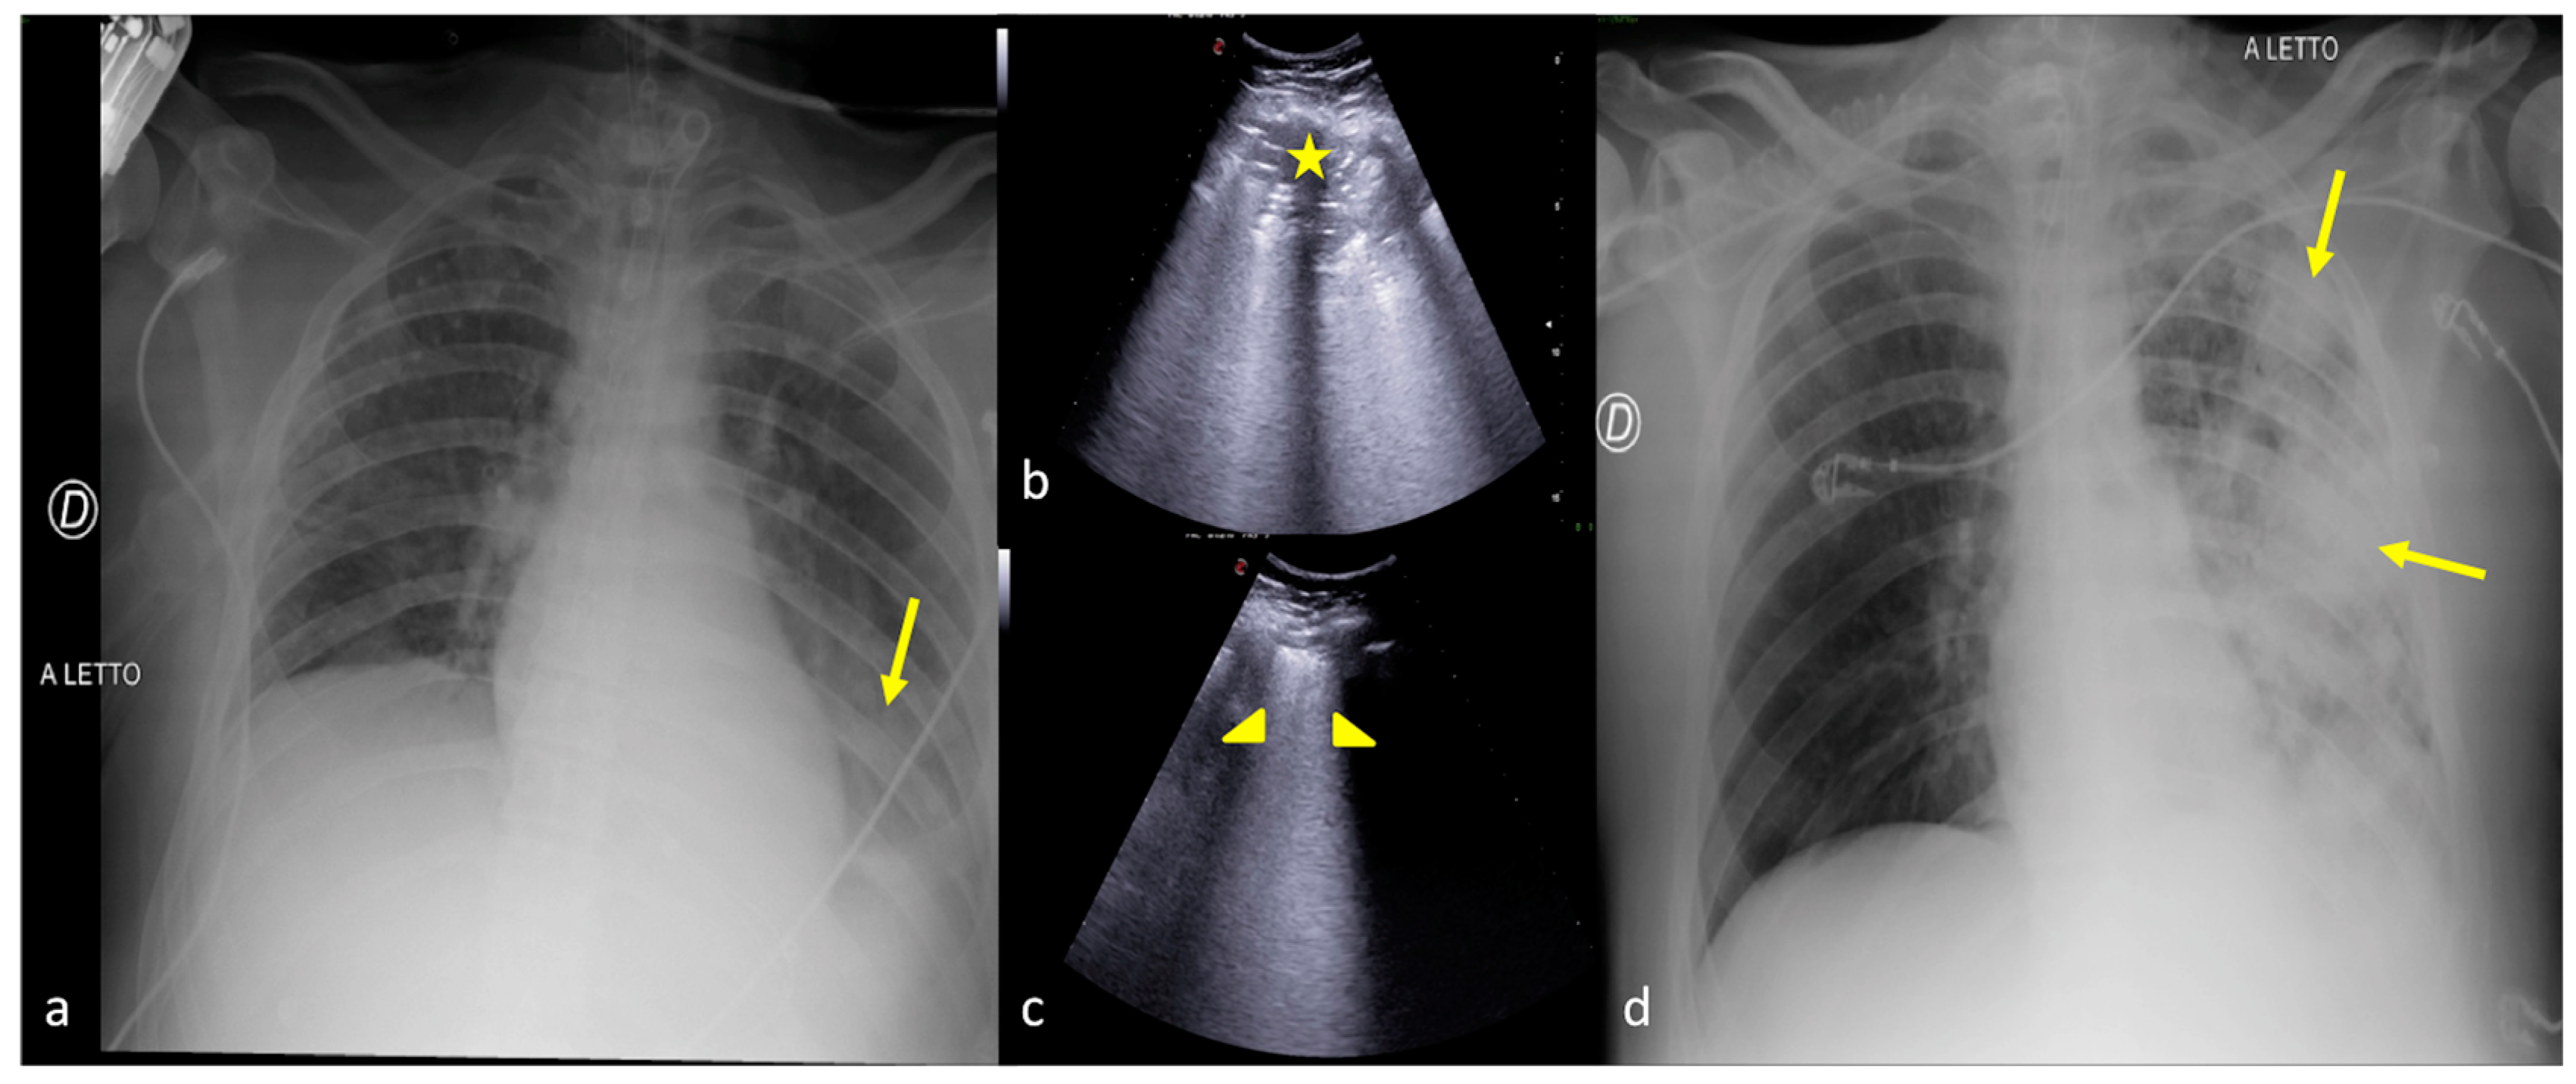

2.3. Pleural Effusion

2.4. Cardiogenic Pulmonary Edema

2.5. Acute Respiratory Distress Syndrome